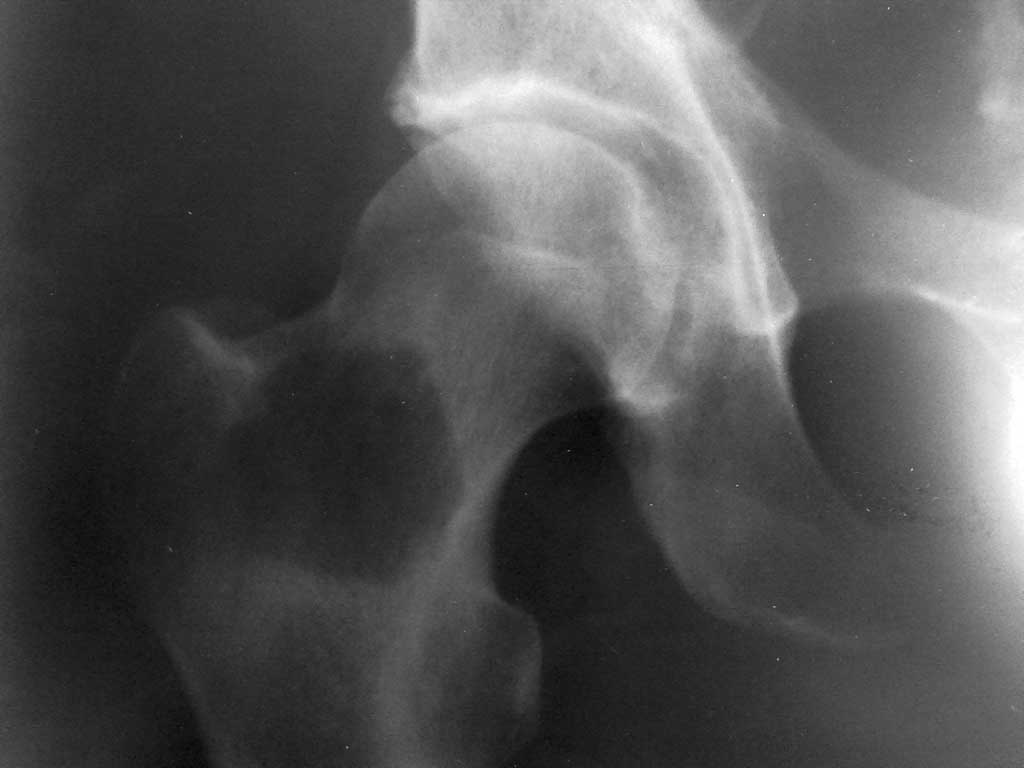

у пациента 54 лет, прооперированного в марте 11г. по поводу рака левого легкого имеется выраженный болевой синдром в области тазобедренного сустава справа.

госпитализирован для дообследования. выявлено новообразование вертельной области. прошу Ваших мнений по тактике лечения. Других метастазов не выявлено. пациент хочет лечиться.

Уважаемый колега! Тактика в данном случае будет зависеть от возможностей данной клиники, принятых стандартах обследования и финансовых возможностей пациента. Данное образование крайне похоже на очаг так называемой фиброзной дисплазии. Однако для уточнения целесообразна в простейшем случае трепанбиопсия из бокового доступа. Если нет данных за малигнизацию образования, то костная пластика (аутокостью из крыла подвздошной, или донорской - не принципиально)была бы наиболее оптимальной и безопасной для пациента. Эндопротезирование имеет смысл только при наличии злокачественной опухоли, но боюсь тогда это пациент онкоортопедов. С уважением А.Т.